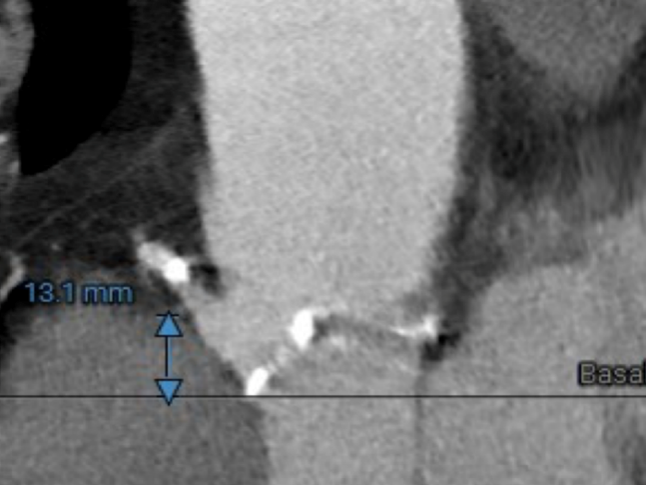

RIGHT CORONARY

右冠开口高度13.1mm